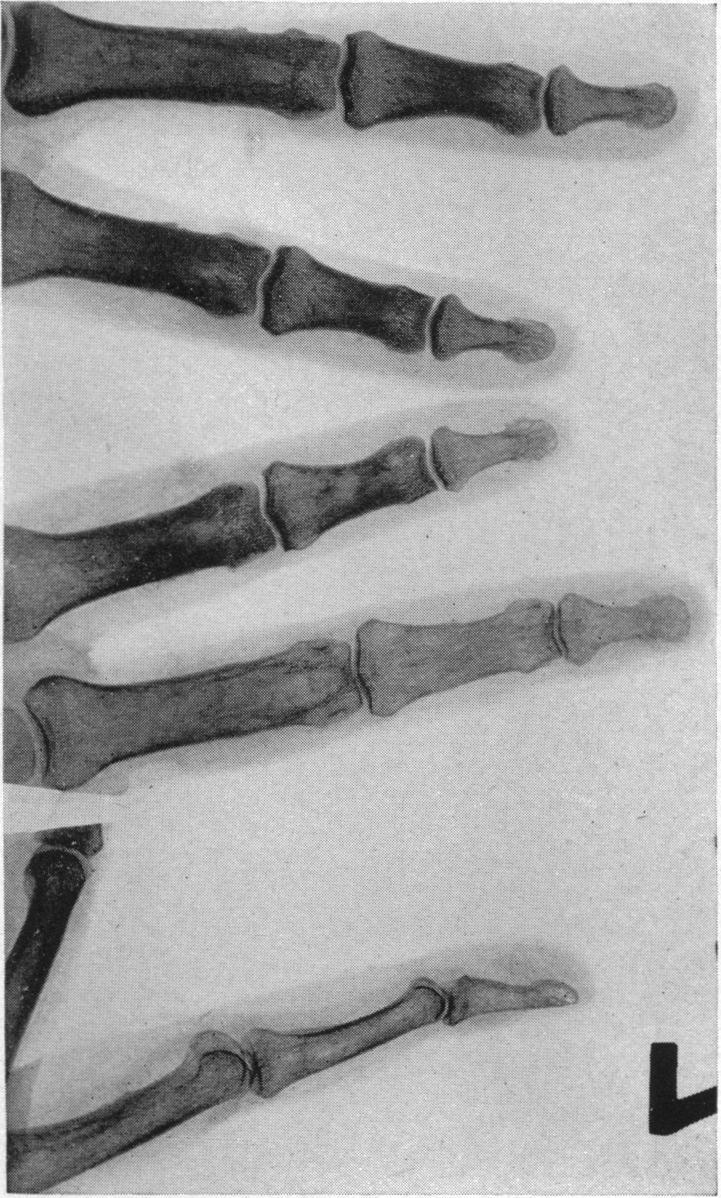

ADVENTITIOUS LIGAMENTS SIMULATING CERVICAL RIBS.

https://cdn.ncbi.nlm.nih.gov/pmc/blobs/3534/1410574/97db51788d8d/annsurg00731-0097-a.jpg